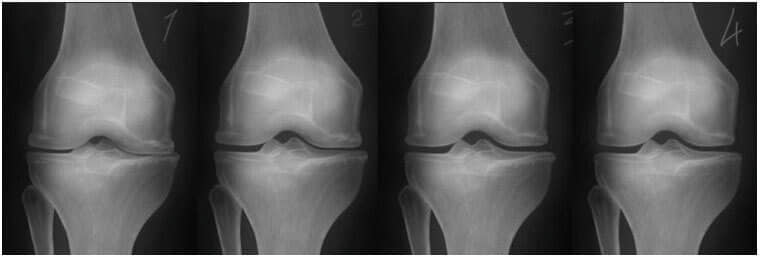

- Slikanje je pokazalo prve znake artroze kolenskih sklepov.

- Z mazilom Motion Free zdravljenje poteka od doma in traja le mesec ali dva. Motion Free pomaga trajno, obnavlja telo na celični ravni. Odpravlja vzroke bolezni in obnovi